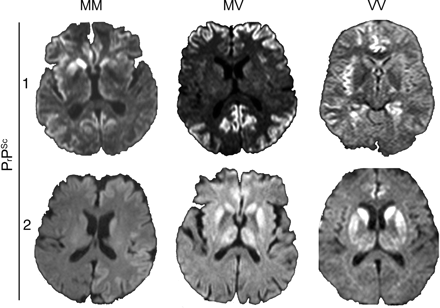

MRI显示例子特点给出亚型的发现图1。的百分比和p显示值用于描述的亚型表1和2和图2。

图1特征核磁共振发现零星克雅二氏症(sCJD)亚型

Diffusion-weighted六sCJD各种分子亚型患者的图像显示基底神经节信号增加和信号额增加,时间,和岛叶皮质(MM1);主要的额叶和顶叶皮层信号增加(1/2 MV1);的扣带回皮质hyperintensities、岛叶皮质和海马体(VV1);基底神经节和广泛的皮质hyperintensities(平方毫米);主要的信号增加基底节和丘脑(MV2);和主要基底神经节信号增加,信号增加扣带回(VV2)。发表在的1/2 MV1映像是J Neuroradiol2008;29:1519 - 1524(©2008美国社会的神经放射学;允许转载)。22VV1图像发表在首页河畔65:1544 2005;1550(©2005企业有限公司;允许转载)。15MV2图像发表在是J Neuroradiol2006;27:1459 - 1462(©2006美国社会的神经放射学;允许转载)。23